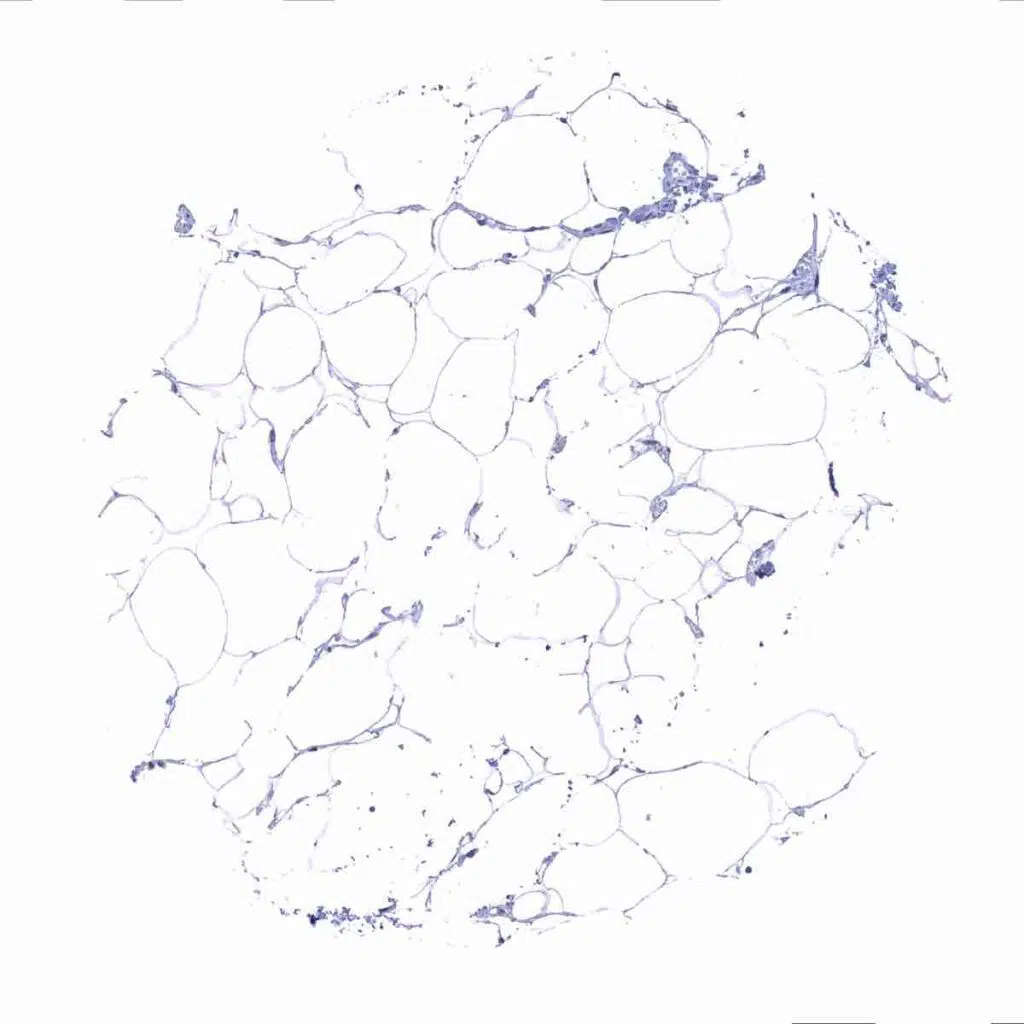

Fat